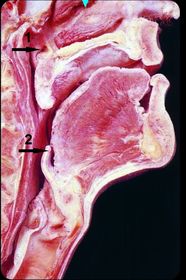

1)identify 1,2,3 2) mention structure related to 4 1) 1- posterior arch of atlas 2- hyoid bone 3- maxillary air sinus 2) pituitary gland.